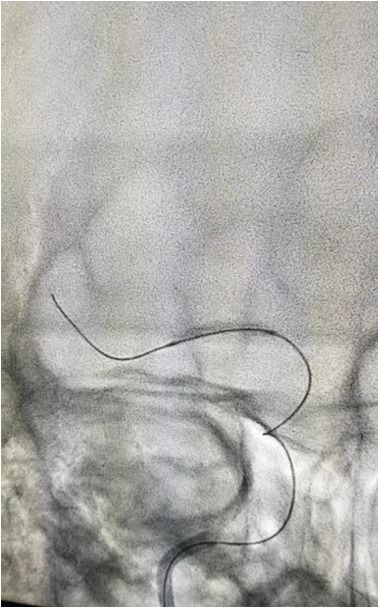

入院后75min,股动脉穿刺成功,后循环造影及右侧颈内动脉正侧位。

导丝导管通过闭塞部位,经微导管造影,证实在远端真腔内,取栓后M1重度狭窄,球囊扩张。

微导丝微导管通过闭塞部位,经微导管造影,确认在远端真腔。